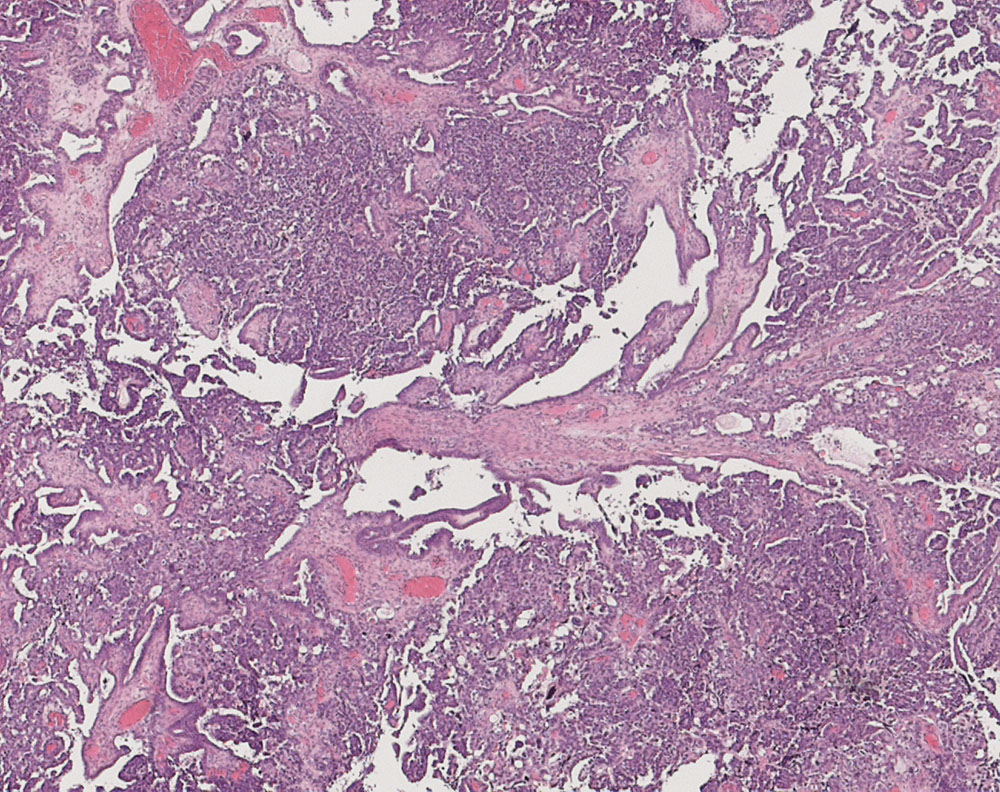

PathoPic ID 10935 - seröses Ovarialkarzinom high grade

seröses Ovarialkarzinom high grade

Papillärer Tumor. Drüsen mit schlitzförmigen Lumina.

Verdacht auf Ovarialkarzinom (CA125 > 2000u/l). CT: Vergrösserte Ovarian beidseits. Maligner Pleuraerguss Adenokarzinom.

Histologie

25